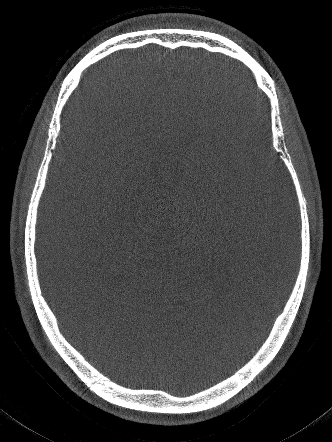

Figure 3 compares the proposed network-based IQM with the entropy-based IQM. The optimization process is identically for both metrics. In an inverse crime scenario both methods can restore the original image quality, however, in a more realistic setting the image entropy is stuck in a local minimum, whereas the network is able to lead the optimization to a nearby motion-free solution.

Refer to captionGt Refer to caption Mo a Refer to captionEnt Refer to captionPro a Refer to captionEnt Refer to caption Pro

Ground Truth (Gt) and Motion Affected Inverse Crime Compensation Clinical Setting (Entropy and Proposed)

Figure 3: Reconstructions of the test patient using [500-2000] HU window. In the inverse crime scenario, the SSIM to the Gt is 0.840.840.84 (Ent/Gt) and 0.950.950.95 (Pro/Gt), respectively for the entropy (Ent) and proposed (Pro) measure. For the more realistic setting (Clinical Setting) the SSIM is 0.650.650.65 (Ent/Gt) and 0.840.840.84 (Pro/Gt), respectively.